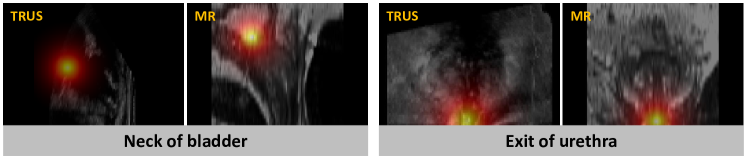

Figure 2: Illustration of the two anatomical landmarks’ distance map used as label for localization network

Anatomically important and stable landmarks are key to registration, as it is to our method. We referred to previous literature [1] and consulted clinicians to finally decide on using four landmarks. Two of the landmarks are the extreme points located on the prostate boundary: the right-most and left-most extreme points observed from the axial view. The other two (shown in Figure 2) are the entrance point of the urethra into the prostate at the neck of the bladder, and the point where the urethra exits the prostate at the prostate apex. As the two extreme points of the prostate boundary can be directly extracted from prostate segmentation, which is available for pre-operative MR and can be predicted with established methods for TRUS, we will focus on the localization of the two other anatomical landmarks: the neck of the bladder, and the exit point of the urethra.